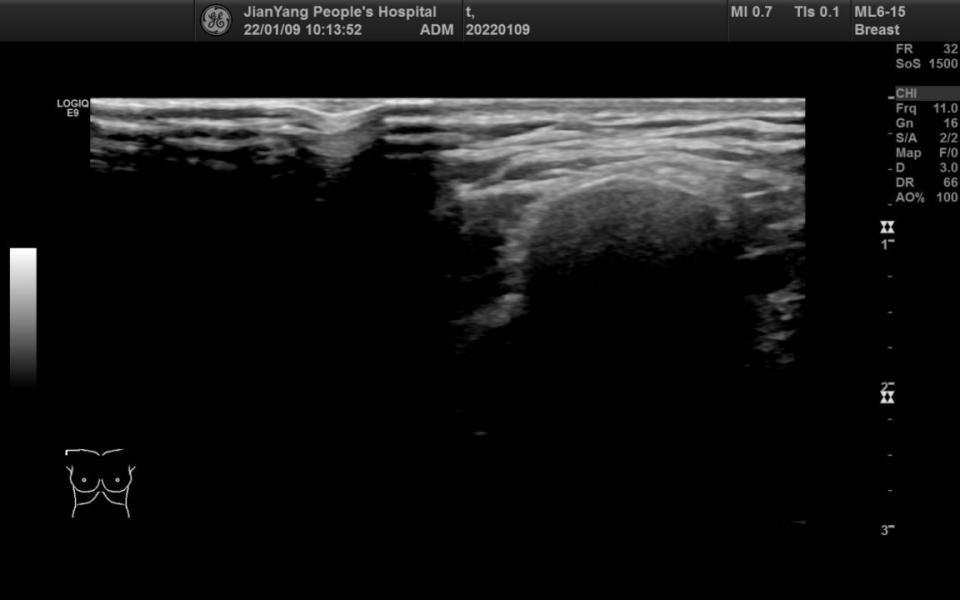

申请超声检查图像如下:

图片图 3 左乳 2 点钟方向肿物

两侧乳房切面形态轮廓正常,层次清楚,腺体回声不均匀,左乳 2 点钟方向距乳头约 20 mm 处可见范围约 28.3 mm x 22.4 mm x 28.1 mm 的低回声团,略呈分叶状,边界清楚,内可见不规则无回声区,其内可见较多条状血流信号。

双乳导管未见明显扩张征像。CDFI:余腺体内未见异常血流信号。

超声提示:左乳低回声团 BI-RADS 4A 类

MBC 多见于绝经后妇女,肿块较大,超声特征多表现为不均匀低回声,边缘光整,形态不规则,平行于皮肤,无钙化或微小钙化,后方回声无改变或增强,伴或不伴腋窝淋巴结转移,Adler 分级 Ⅱ~Ⅲ 级多见,阻力指数多>0.7。与间叶化生癌相比,鳞状细胞癌多表现为直径较大、呈囊实性回声、腋窝淋巴结无转移。